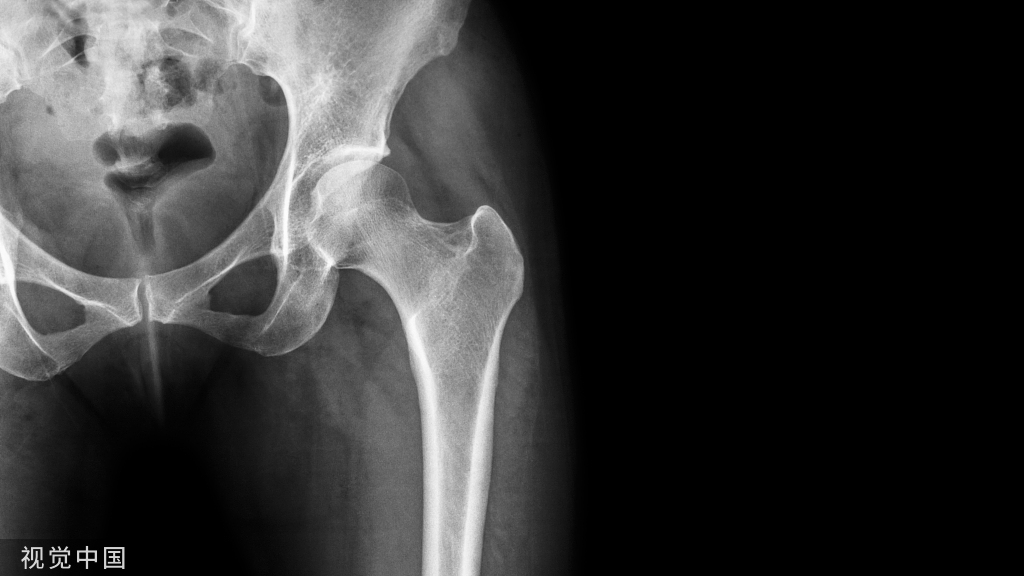

图 1-37 掌侧接骨板固定桡骨远端骨折 A. 桡骨远端骨折术前正侧位X线片, 显示远端向掌侧移位;B. 术后正侧位X线片, 显示骨折复位良好,腕关节间隙良好